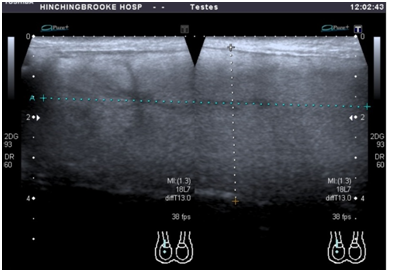

Post excisional inspection confirmed a hard yellowish-white mass, mixed with fatty tissue, enclosed in a pseudo-capsule. This was arising from the spermatic cord. The testicle looked entirely normal, but was impossible to be spared due to oncological principles (Figures 2‒4). The pathology report confirmed a 90x60x53mm Sclerostin liposarcoma of the spermatic cord pT2bNxMx, grade 1, with clear surgical margins. The sections show a relatively well circumscribed tumour composed predominantly of numerous variously sized adipocytes with occasional lipoblasts and scattered large atypical cells. There is also a prominent hyalinized and sclerotic fibrous tissue component which also contains more spindled and atypical nuclei. No necrosis or de-differentiated areas were seen. The patient was followed up by the sarcoma specialist team, and had recovered very well after surgery.

Figure 2 solid mass arising from the spermatic cord.

Figure 3 solid mass removed with normal looking testicle and epididymis.